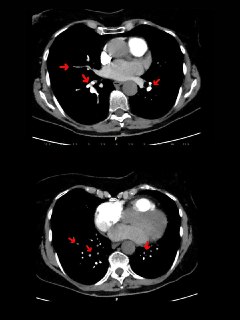

STEMI: багатосудинне ураження/ невдала спроба стентування — механічне ускладнення ІМ: аневризма верхівки ЛШ (на ЕКГ «зас...